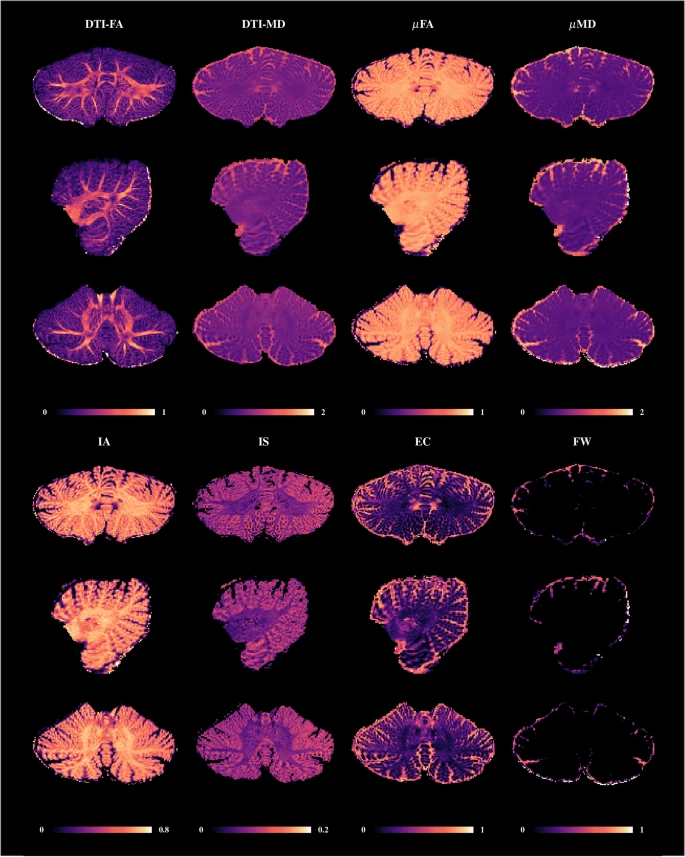

IMAGE SOURCE: A multimodal submillimeter MRI atlas of the human cerebellum

Another way to think of it is that it is really wrinkly, or highly striated (striped), with each wrinkle called a folia (Latin for “leaves”). The folia allow the cerebellum to have an incredibly large surface area, keeping lots of neurons packed into a very small space. Together with the large surface area, the fact that most of the cerebellar neurons are exceptionally tiny makes for its huge number of cells.

Cerebellar cortex is layered

The cerebellar cortex is composed of three main layers.

The molecular layer is the outermost layer where parallel fibers of granule cells will synapse with (pass a message to) the dendritic arbors of Purkinje cells. Below the molecular layer is the Purkinje layer, made up of cell bodies from the Purkinje cells. Then below the Purkinje layer is the granular layer. Can you guess what’s there? It’s the layer made up of the cell bodies of granule cells, and is where mossy fibers from the pontine nuclei, spinal cord, and the vestibulocochlear nerve synapse with the granule cells. These mossy fibers are carrying signals into the cerebellum, and they stimulate the granule cells, which will then send messages up their axons to their parallel fibers, which will signal the Purkinje cells.

Typically, the cerebellum is displayed as if it is one solid round structure, almost like a baseball. One thing I found to be interesting, however, is that it is really shaped more like a flat sheet or long oval that has been rolled up into itself, making it appear more rounded. This rolled up structure further increases the surface area of the cerebellum and helps allow for its incredible cell number.